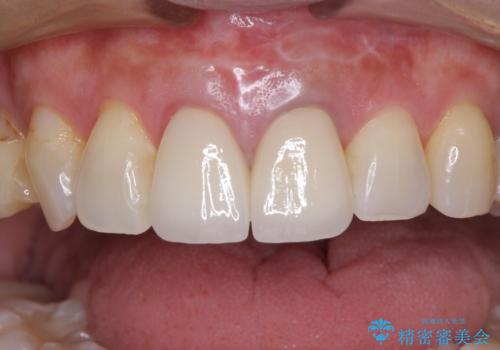

見栄えの悪い仮歯 前歯のオールセラミック治療

まずは審美的な仮歯を装着し、根管治療を行った後にオールセラミッククラウンにて補綴治療を行うこととしました。

根管治療後に痛みは軽減しましたが、僅かな痛みが続くとのことで、レントゲン写真では病変は認められなかったものの、歯根端切除を行うこととしました。処置後は痛みは全くなくなり、安心して補綴治療を行うことができました。